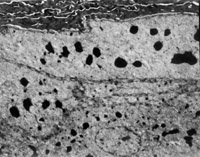

經(jīng)MEBT/MEBO治療20天,電鏡觀察到基底細(xì)胞層與纖維母細(xì)胞之間的半橋粒連接,同時(shí)可見(jiàn)纖維母細(xì)胞內(nèi)粗面內(nèi)質(zhì)網(wǎng)結(jié)構(gòu)和線粒體增生活躍(圖5-3-19~5-3-21)。 MEBT/MEBO治療30天后,上皮組織再生修復(fù),已基本完成,創(chuàng)面組織切片顯示膠原纖維成熟,排列整齊(圖5-3-22),直徑為0.1~0.5祄,并可見(jiàn)明暗相間周期性橫紋(64nm),未見(jiàn)到膠原纖維扭曲和呈旋渦、菜花等病理形態(tài)。

5-3-22 MEBT/MEBO治療30天,整齊排列的膠原纖維,纖維均勻一致直 徑 0.1~0.5祄,有明暗相間的周期性橫紋(64nm)